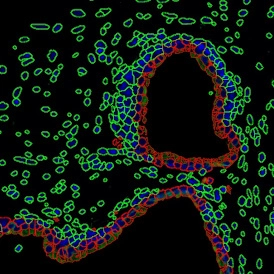

Investigating T-Cell Communities in Immune Tissues with StrataQuest 8

Multiplex fluorescence imaging of tonsil tissue analyzed in StrataQuest to quantify and map T-cell subsets within and around germinal centers.